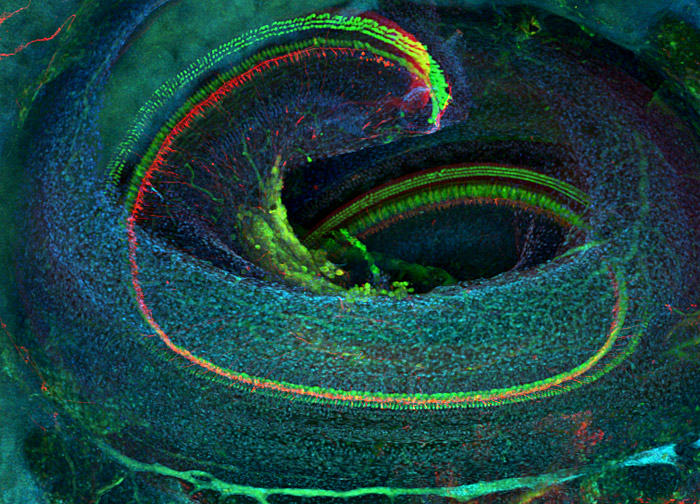

Specimen: Mammalian Inner Ear

Technique: Confocal